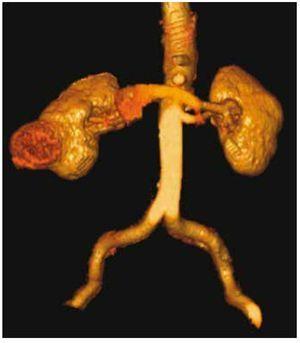

Cuenta como antecedente de importancia: hipertensión de 15 años de evolución en tratamiento con enalapril una tableta cada 8 horas, además de exposición crónica a productos del antimonio inhalado por su trabajo como soldador ahora ya pensionado, como factores de riesgo6,7, niega alguna otra enfermedad crónica, pérdida de peso ponderal o síntomas constitucionales, refiere nunca haber fumado. Se realiza entonces tomografía computada (TC) abdominopélvica simple y contrastada, encontrando tumor renal heterogéneo de 50 x 45.9 mm, invadiendo desde cáliz medio hasta espacio cortical, la cual tiene realce periférico de medio de contraste (figs. 2 y 3), sin evidencia de metástasis torácica o local, vejiga sin lesiones ocupantes. Se realiza además pruebas de laboratorio complementaria reportando Hb: 12.6 g, Hto: 35.6%, plaquetas: 142,000, leucos: 8.4, glucosa: 120 mg, urea: 53 mg, creatinina: 1.04 mg, tiempos de sangrado y pruebas funcionales hepáticas dentro de parámetros normales. Uroanálisis: leucocitos 0 por campo, eritrocitos 0 por campo, bacterias proteínas y nitritos negativo.

Figura 2. Corte topográfico donde se muestra una lesión sólida de 4.5 x 5.0 cm, en su borde externo del riñón derecho con densidad heterogéneo.

Figura 3. Vista posterior en reconstrucción 3D.